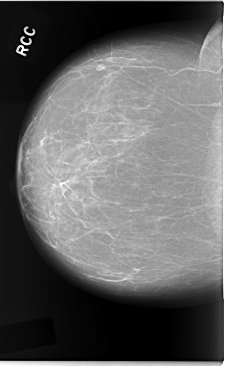

C_0042_1.RIGHT_CC

RIGHT_CC LINES 5848 PIXELS_PER_LINE 3600 BITS_PER_PIXEL 12 RESOLUTION 50 NON_OVERLAY